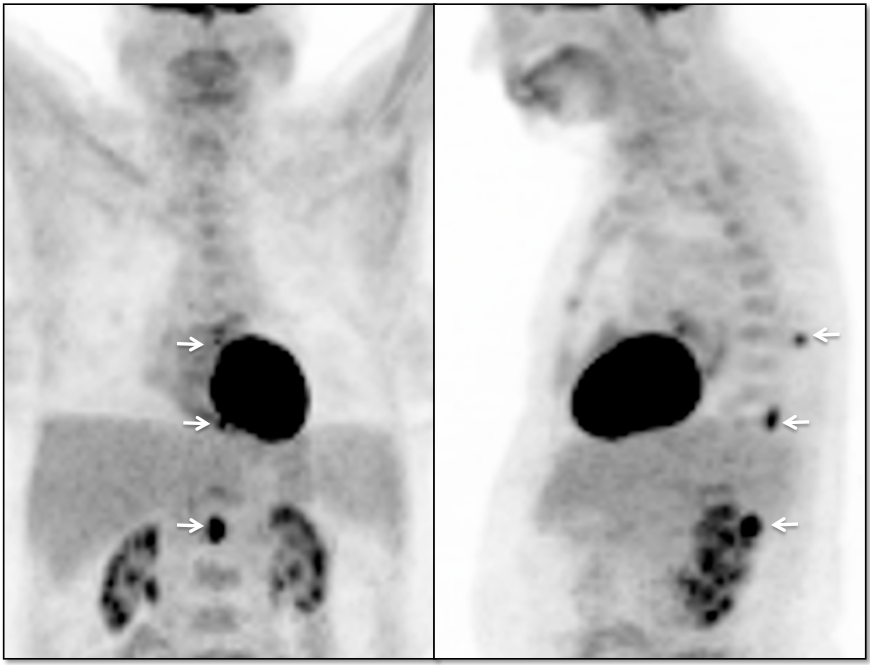

- Primary lesions are rarely evaluated with PET/CT.

- Metastatic lesions are not uncommon, appearing very focal, with uptake > liver activity.